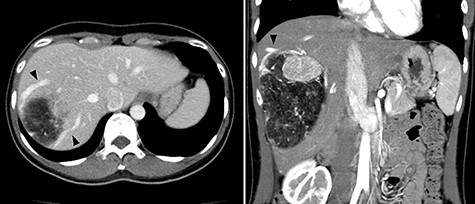

A 45-year-old woman was referred to our hospital with a huge liver tumor, which had been diagnosed as HAML 5 years previously when it was 12 cm in diameter (Fig. 1). Periodic follow-up with ultrasound and magnetic resonance imaging after the initial diagnosis had shown a progressive increase in the size of the tumor, and by the time of referral it measured 20 × 14 cm and had become symptomatic. On admission, enhanced computed tomography revealed a very large, well-defined, mixed-density mass occupying the entire right lobe of the liver (Fig. 2). Angiography showed dilated and tortuous vessel inside the tumor, and a drainage vein from the tumor to the right hepatic vein was visualized in the early phase (Fig. 3).

Abdominal computed tomography (CT) 5 years before referral to our hospital; enhanced CT revealed mixed density tumor measuring 12 × 10 cm in the right lobe of the liver; a peritumoral early drainage vein around the tumor (arrow heads) was visualized.

Abdominal CT on admission; the tumor had enlarged, occupying the entire right lobe of the liver, and measuring 200 × 140 × 120 mm.